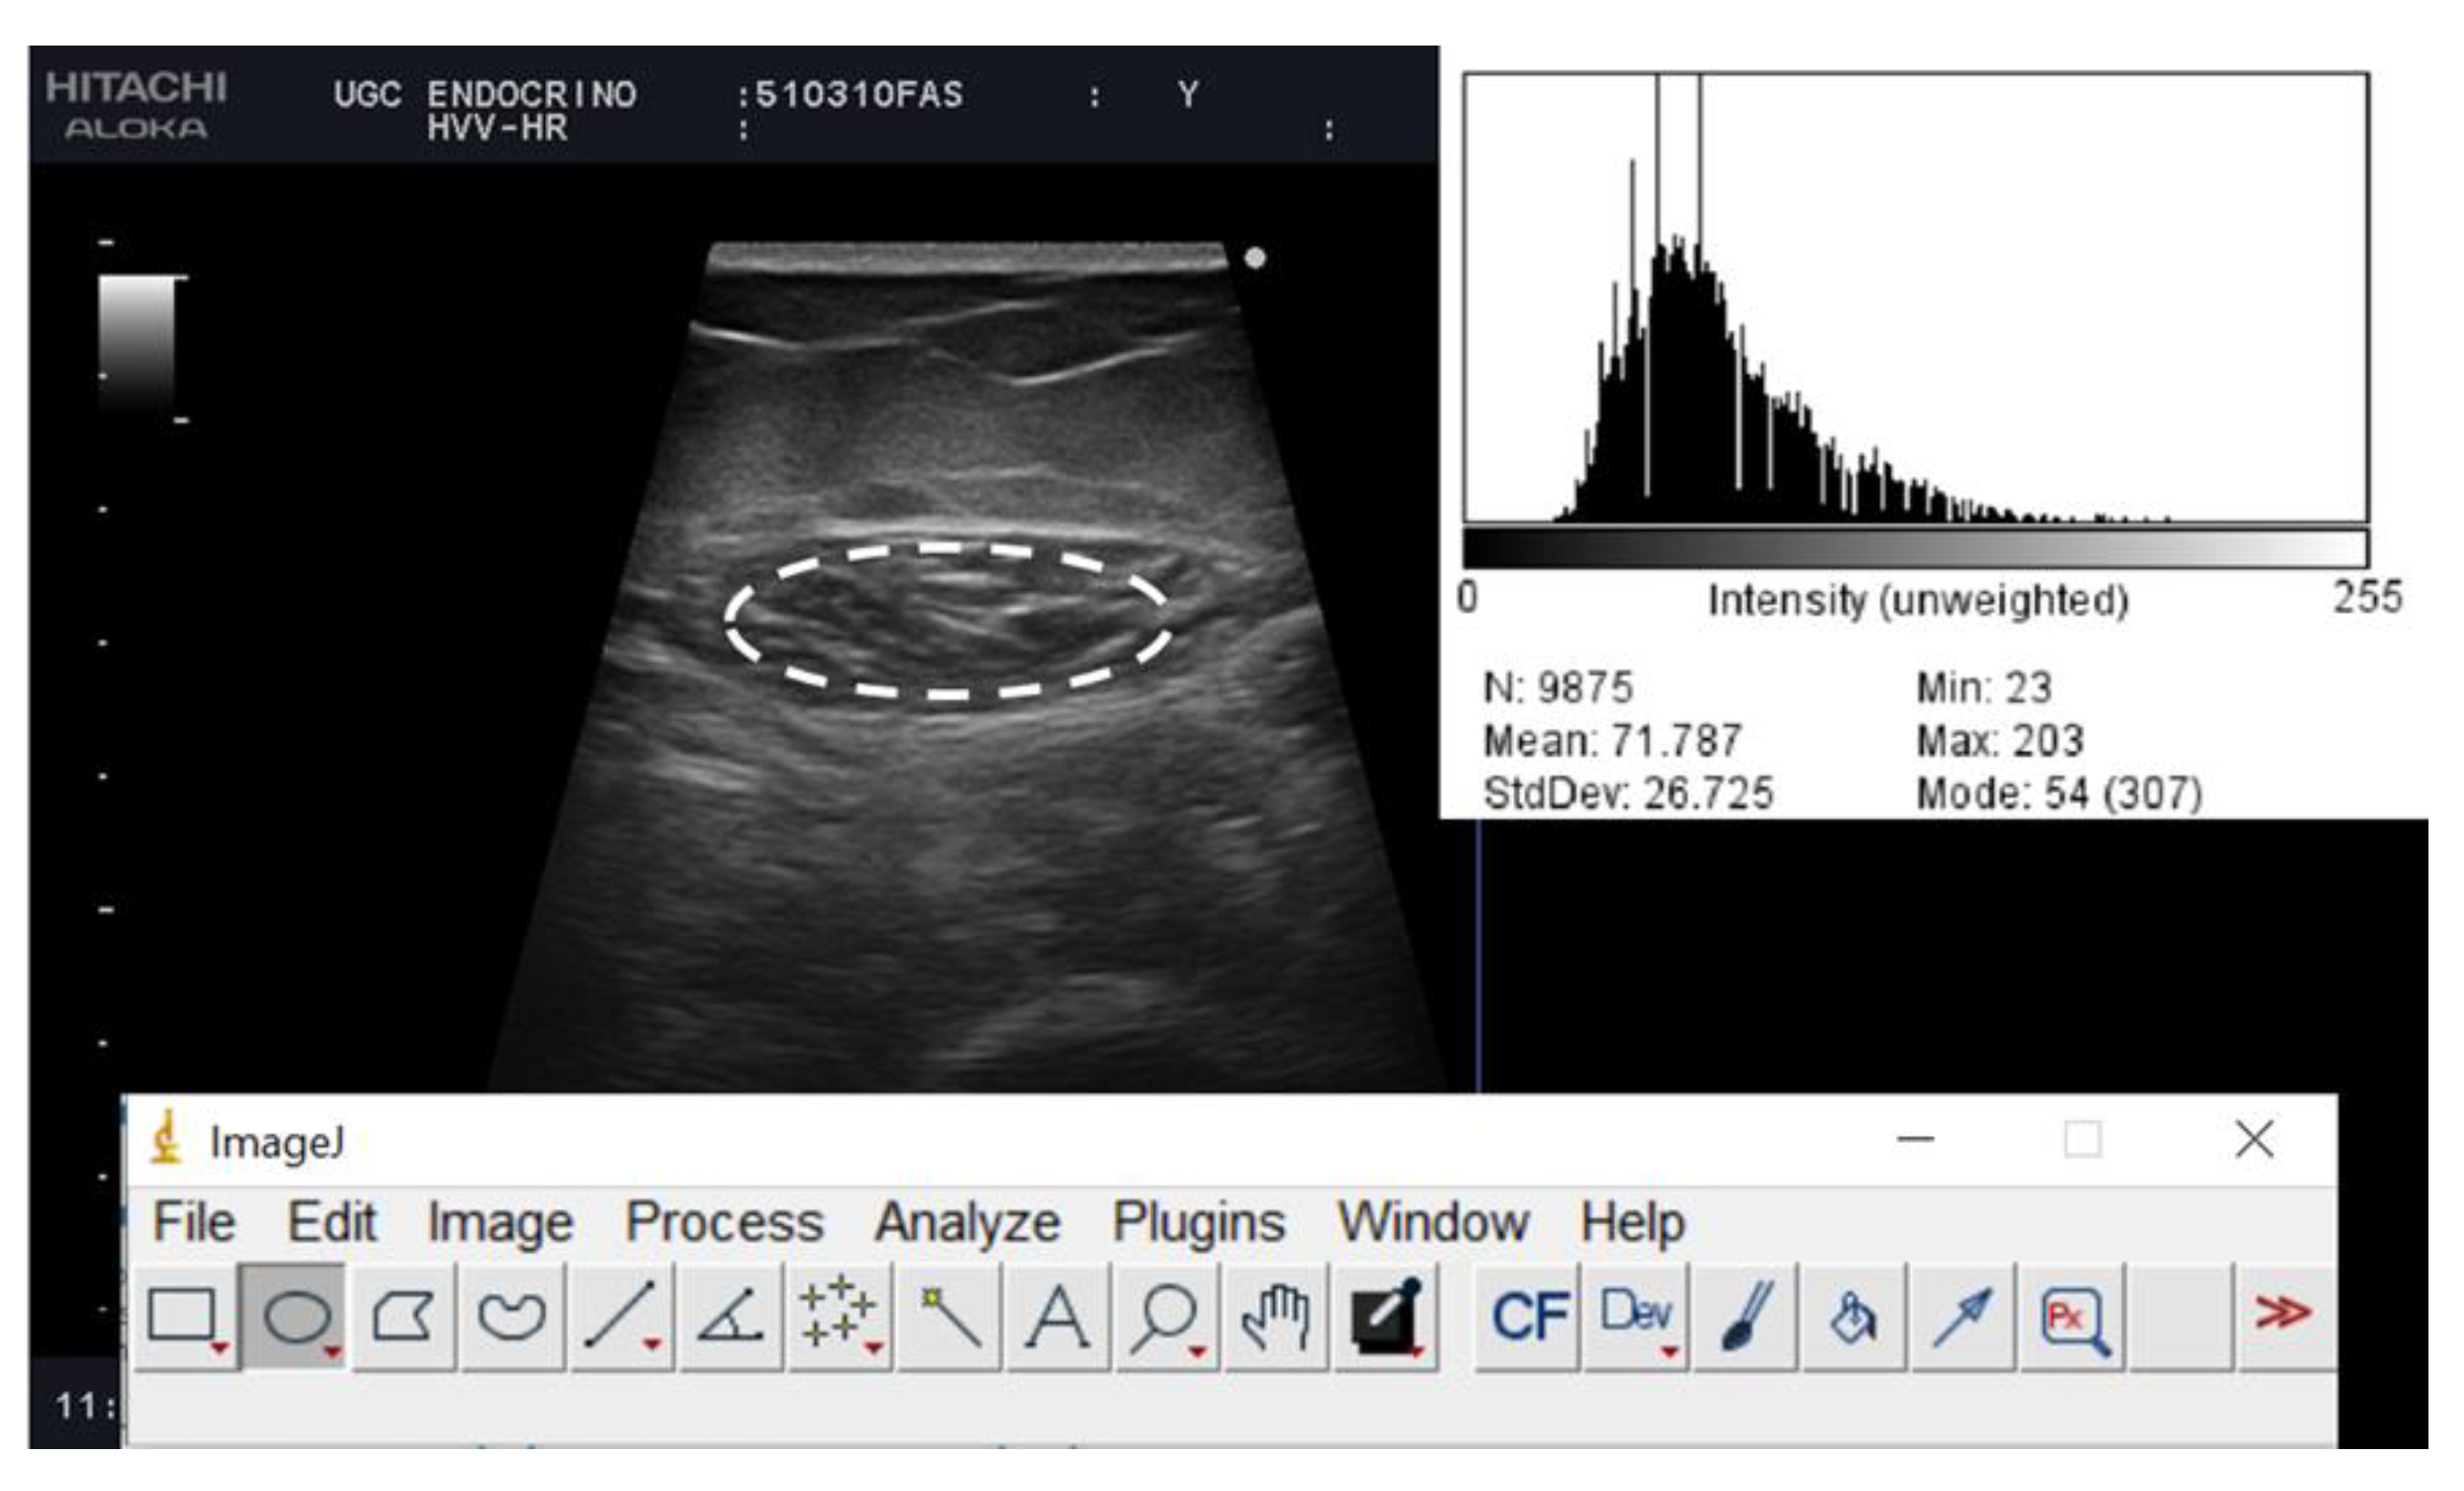

Rectus Femoris (RF) Ultrasound Assessment

| Qualitative parameters | |||||

| Mean Echo intensity | 73.28 (50.69–81.8) | 69.09 (47.60–78.09) | 79.11 (56.98–93.15) | 0.296 | |

| Minimum echo intensity | 12 (0.25–27) | 12 (0–24.5) | 12 (5–34) | 0.321 | |

| Maximum echo intensity | 184 (176.25–203.75) | 187 (177–207.5) | 177 (170–196) | 0.090 | |